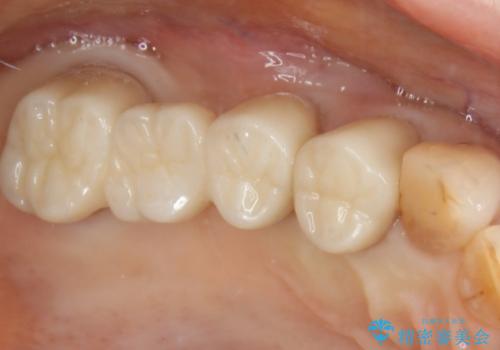

部分矯正とセラミッククラウンですきっ歯・矮小歯を効率的に治す

- 初診時、前歯部の見た目の改善を主訴にご来院されました。生まれつき歯が小さい状態の「矮小歯」とそれに伴う正中の「すきっ歯」があるため、大きなガタつきはないものの笑った時の印象に違和感が出る状態となっていました。

矮小歯が傾斜していることなどを踏まえ、より安全に治療を進めるために部分矯正を併用したセラミッククラウンでの治療を行うこととなりました。

矮小歯の補綴治療

前歯や小臼歯では、生えてくる歯が小さく審美的に影響が出る場合があります。このような歯を矮小歯(わいしょうし)と言います。

今回のケースでは、歯が小さいだけでなく傾斜もしていたため補綴治療時に歯を削ることで神経の症状が出る可能性がありました。そのため、事前に部分矯正を行い歯軸の改善を行っておくことで、歯髄を温存することができました。